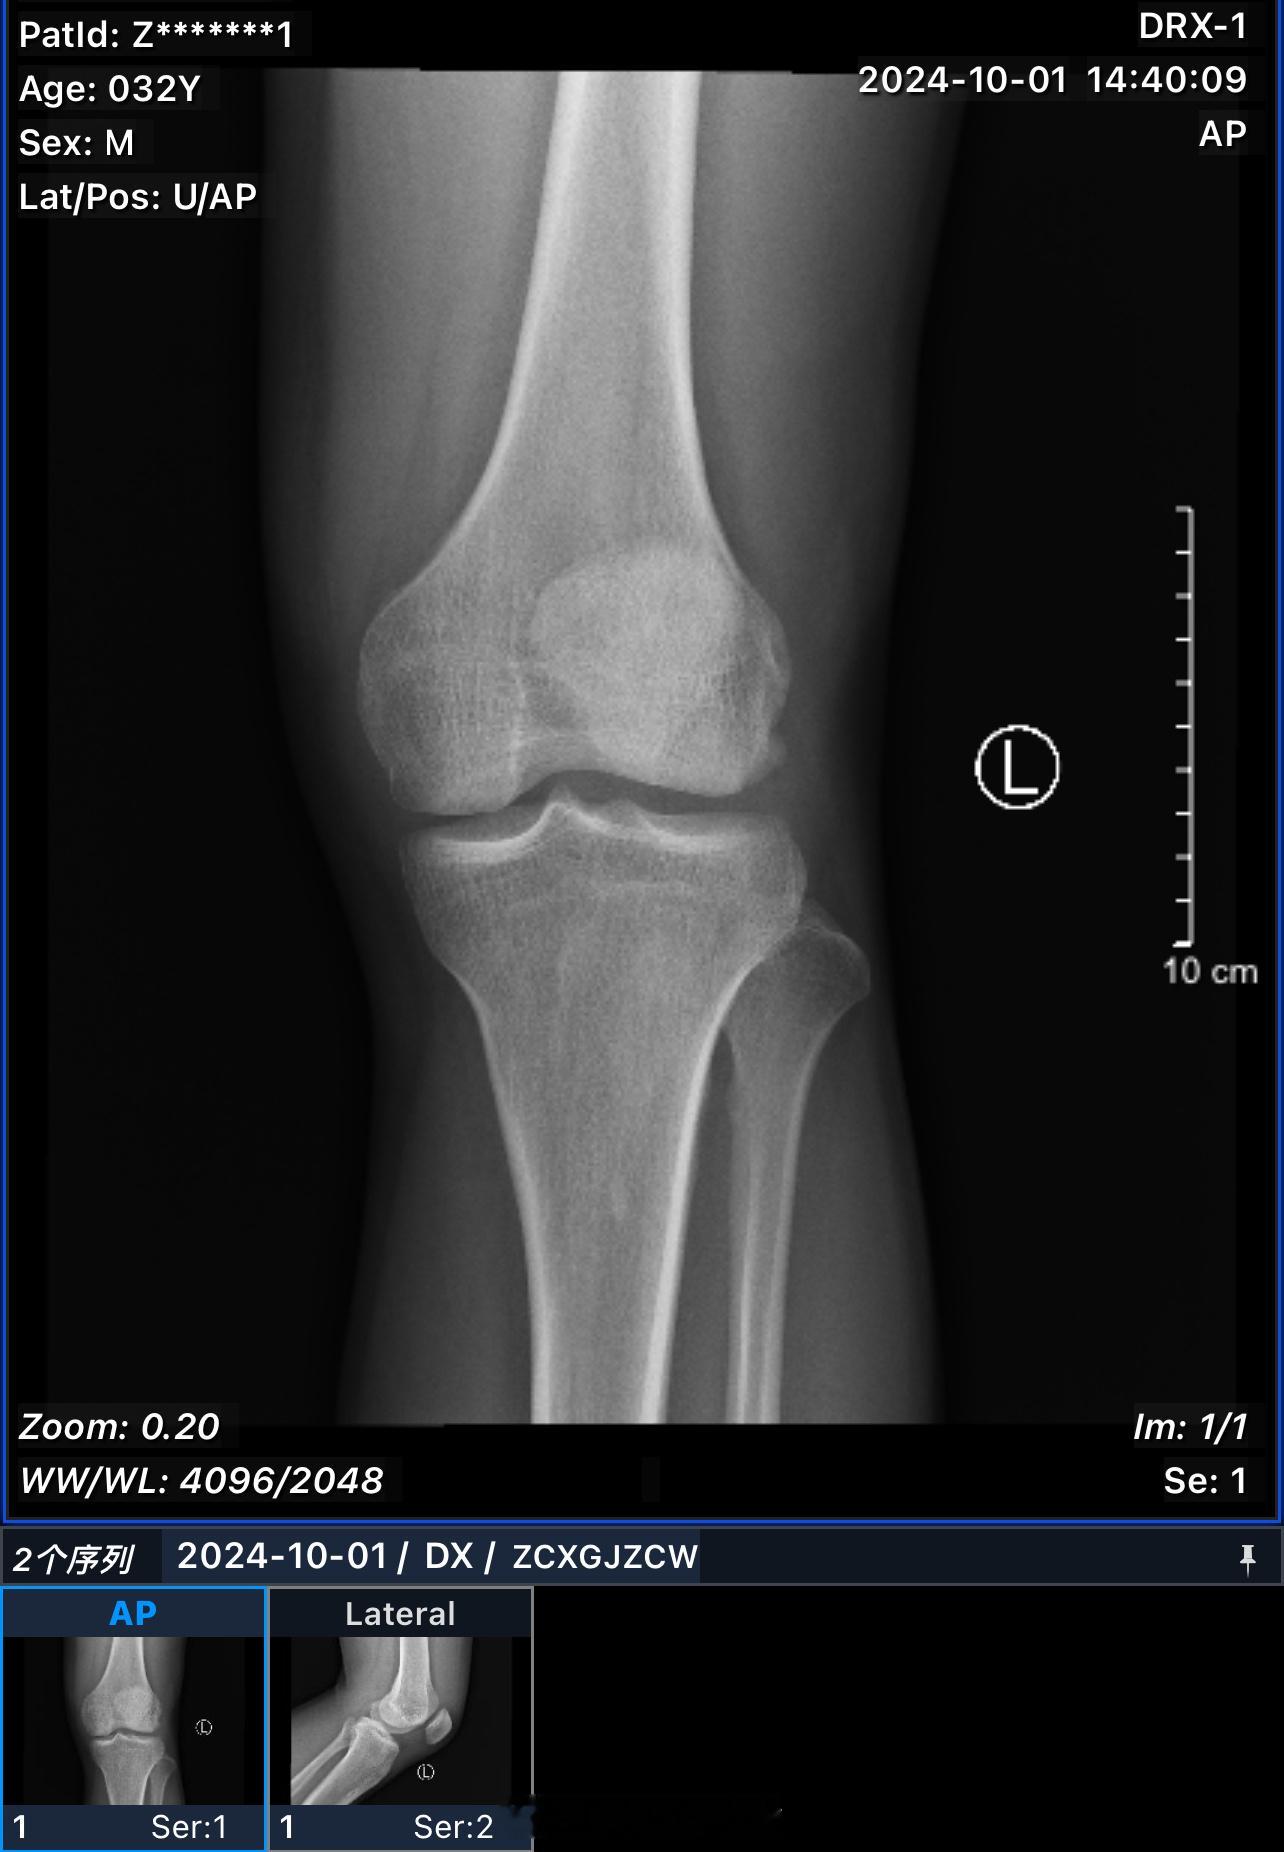

希望有惊无险,吓吓我就可以了。以后一定不逞强!已经30多岁了。欲速则不达,胜负欲

希望有惊无险,吓吓我就可以了。以后一定不逞强!已经30多岁了。欲速则不达,胜负欲也该降降了,希望兄弟们打球过程中,也要注意安全,不要强干,健康很重要 ​​​